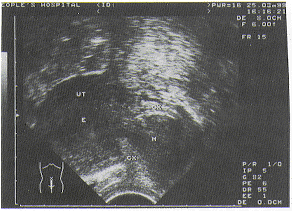

Ⅰ型为单纯局限型3例肌瘤局限于宫腔内,超声表现:子宫正常大小或稍大,表面光滑,质地均匀,宫腔内有低回声团直径0.5~2cm,一般为单发、无蒂,如宫腔少许积血时,可清晰看到肿瘤周边有一圈低回声晕(图1)。

UT:子宫,E:内膜,EM:粘膜下肌瘤

图1 Ⅰ型单纯粘膜下肌瘤腔内型